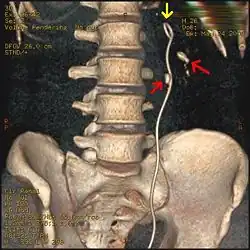

Otherwise a noncontrast helical CT scan with 5 millimeters (0.2 in) sections is the diagnostic method to use to detect kidney stones and confirm the diagnosis of kidney stone disease.[16][57][61][66][7] Near all stones are detectable on CT scans with the exception of those composed of certain drug residues in the urine,[59] such as from indinavir.

Where a CT scan is unavailable, an intravenous pyelogram may be performed to help confirm the diagnosis of urolithiasis. This involves intravenous injection of a contrast agent followed by a KUB film. Uroliths present in the kidneys, ureters, or bladder may be better defined by the use of this contrast agent. Stones can also be detected by a retrograde pyelogram, where a similar contrast agent is injected directly into the distal ostium of the ureter (where the ureter terminates as it enters the bladder).[61]